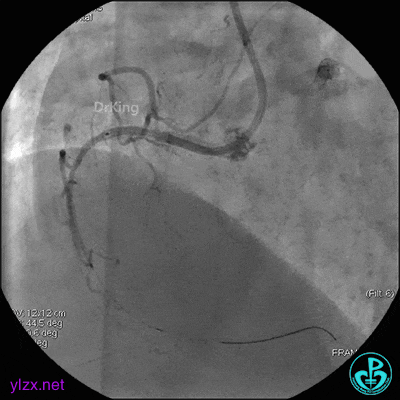

6 二次治疗

1周后复查造影,见粗大前降支3级血流,近端严重狭窄伴管壁严重钙化影,病变累及前降支开口。

球囊扩张后前降支中段植入支架。

前降支近端串联植入支架,前降支开口支架精确定位。

支架内非顺应性球囊后扩张。

最后造影结果显示前降支3级血流,支架膨胀尚可。